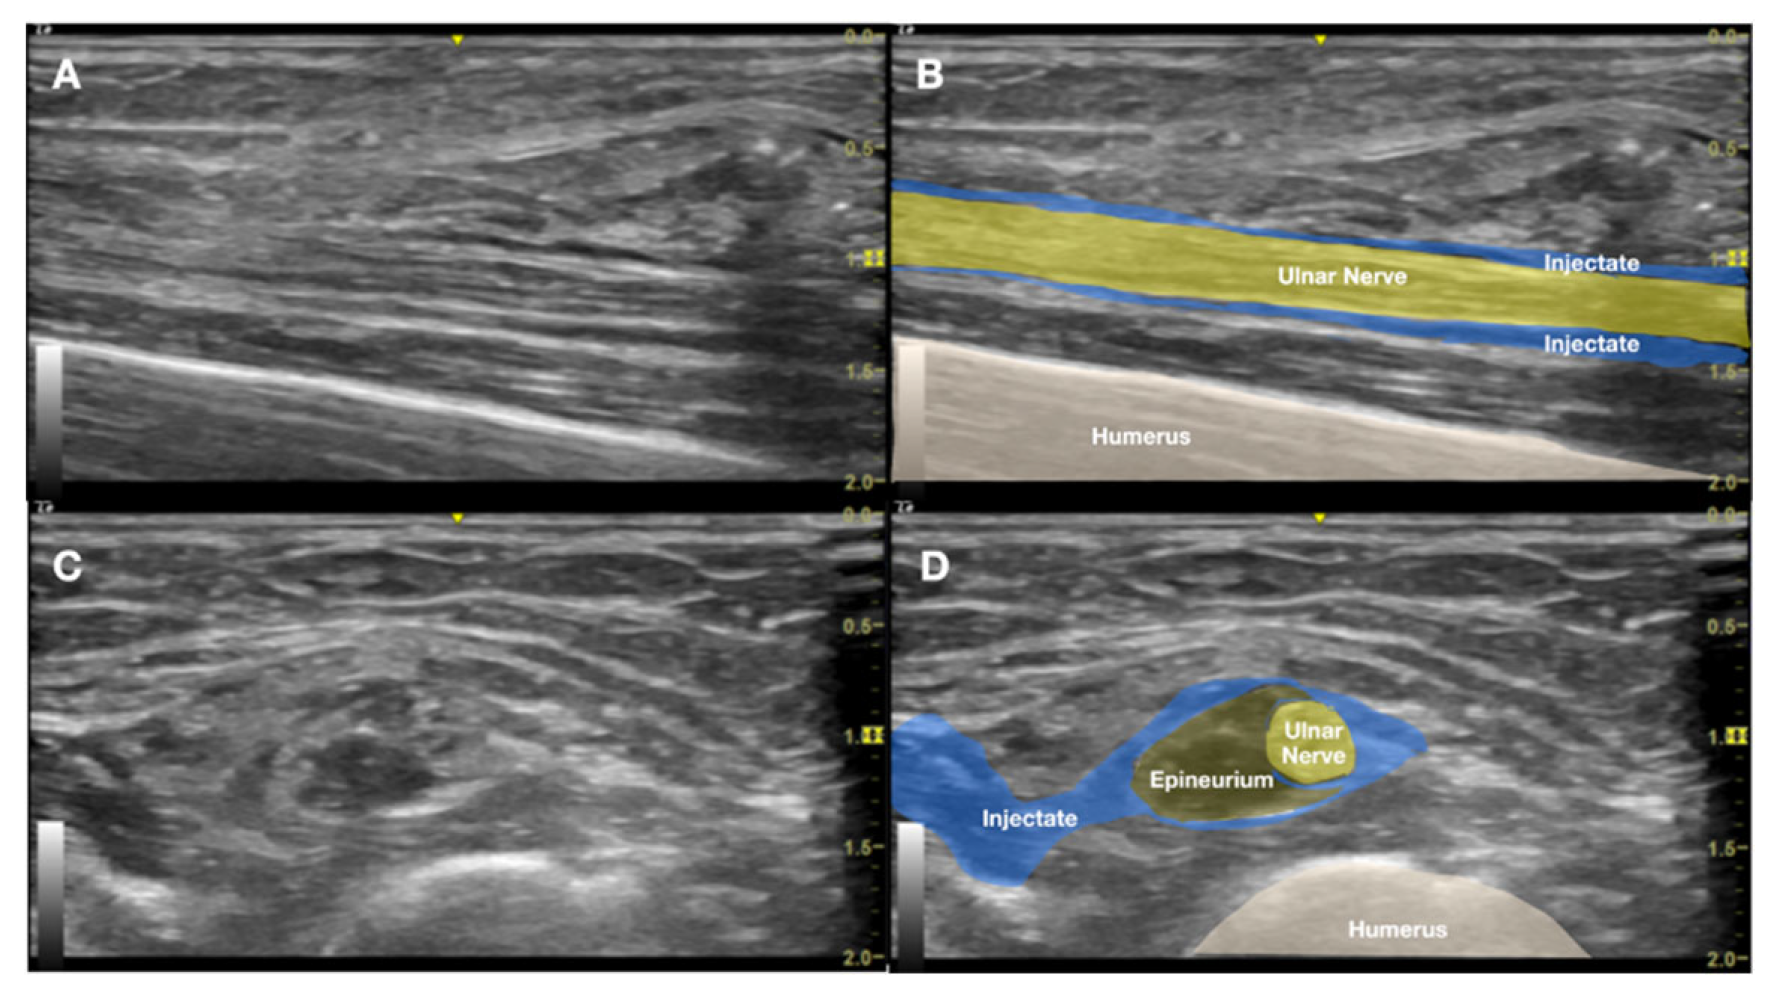

Figure 6. Ultrasound-guided hydrodissection of the distal aspect of Implanon® using dextrose 5% in water (D5W) without local anesthetic. The injectate creates a hypoechoic fluid plane between the implant and the adjacent ulnar nerve, facilitating both mechanical separation and biochemical relief of perineural inflammation. A, Ultrasound image; B, labeled explanation.

The procedure was performed on the same first day of the visit, under local anesthesia in an outpatient interventional suite. With the patient positioned supine and the left arm abducted, the team re-explored the previous incision site under sterile conditions. US confirmed the retained Implanon 2cm distal to one of the incision sites, immediately adjacent to the ulnar nerve. Initial direct US-guided removal attempts were unsuccessful due to significant nerve irritation triggered by manipulation. To address this challenge, approximately 50 mL of 5% dextrose in water (D5W) without local anesthetic (LA) was injected via US-guided HD at the distal aspect of the implant. This approach aimed to achieve both a biochemical anti-inflammatory effect and mechanical separation between the implant and the adjacent nerve (Figure 6). The HD technique successfully created a protective fluid buffer around the neural structures.

Despite ulnar nerve protection achieved with D5W HD, the implant could not be secured due to its low-friction surface and evaded capture with mosquito forceps under US-guidance. Subsequent fluoroscopic correlation using C-arm imaging confirmed iatrogenic proximal migration of the implant toward the axillary region. Under combined US-fluoroscopic guidance, the implant was re-identified in the proximal upper arm. A second targeted HD session was performed under US guidance, during which an additional 50 mL of D5W without LA was injected from proximal to distal along the anticipated tract to facilitate distal repositioning of the implant back to the distal arm. To overcome the technical challenge of further implant mobility during the second trial, the proximal tip of the implant was percutaneously penetrated and stabilized using a 25-gauge (G) needle under US guidance (Figure 5B). This innovative stabilization technique enabled secure grasping of the implant with mosquito forceps and successful extraction through the previous incision under real-time US visualization (Figure 5C).